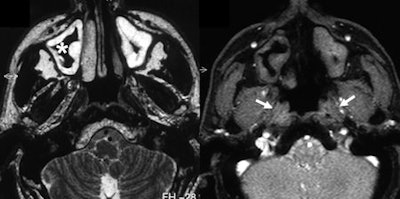

Lesions such as nasopharyngeal carcinoma or hyperplastic mucosal swelling, for example, can lead to dysfunction of the eustachian tube so that its physiological tasks are restricted. Without its correct aperture, there is no efficient ventilation, no drainage of the middle ears' secretions, and no protection from excessive sound pressure and pressure differences, all of which can lead to reduced hearing ability, infections, or other middle ear diseases.

It was possible to evaluate the opening of the eustachian tube during the Valsalva maneuver in all patients. Within the same examination, an underlying problem was identified and its extent delineated in 14 of the 16 patients. In all patients, the anatomical landmarks and structures were clearly depicted and differentiated from pathological abnormalities in the T2-weighted sequence. Involvement of the anatomical structures could be assessed, but the osseous part of auditory tube was depicted with less good image quality than the other parts. In this region, the amount of soft tissue is small and consists only of the mucous membrane, connective tissue, and the periosteum.

"Visualization of the eustachian tube by MRI constitutes a method unifying imaging, function, and evaluation of pathological findings. Dysfunctionality of the nasopharyngeal tube can be assessed and correlated to its cause in one single examination without any invasive investigations," the authors concluded. "Assessing tubal function is of considerable importance in the preoperative evaluation of patients with chronic otitis media or tympanic effusion, since planning of the operation depends on tubal function. Recovery of tube patency is necessary for prevention of future infections."